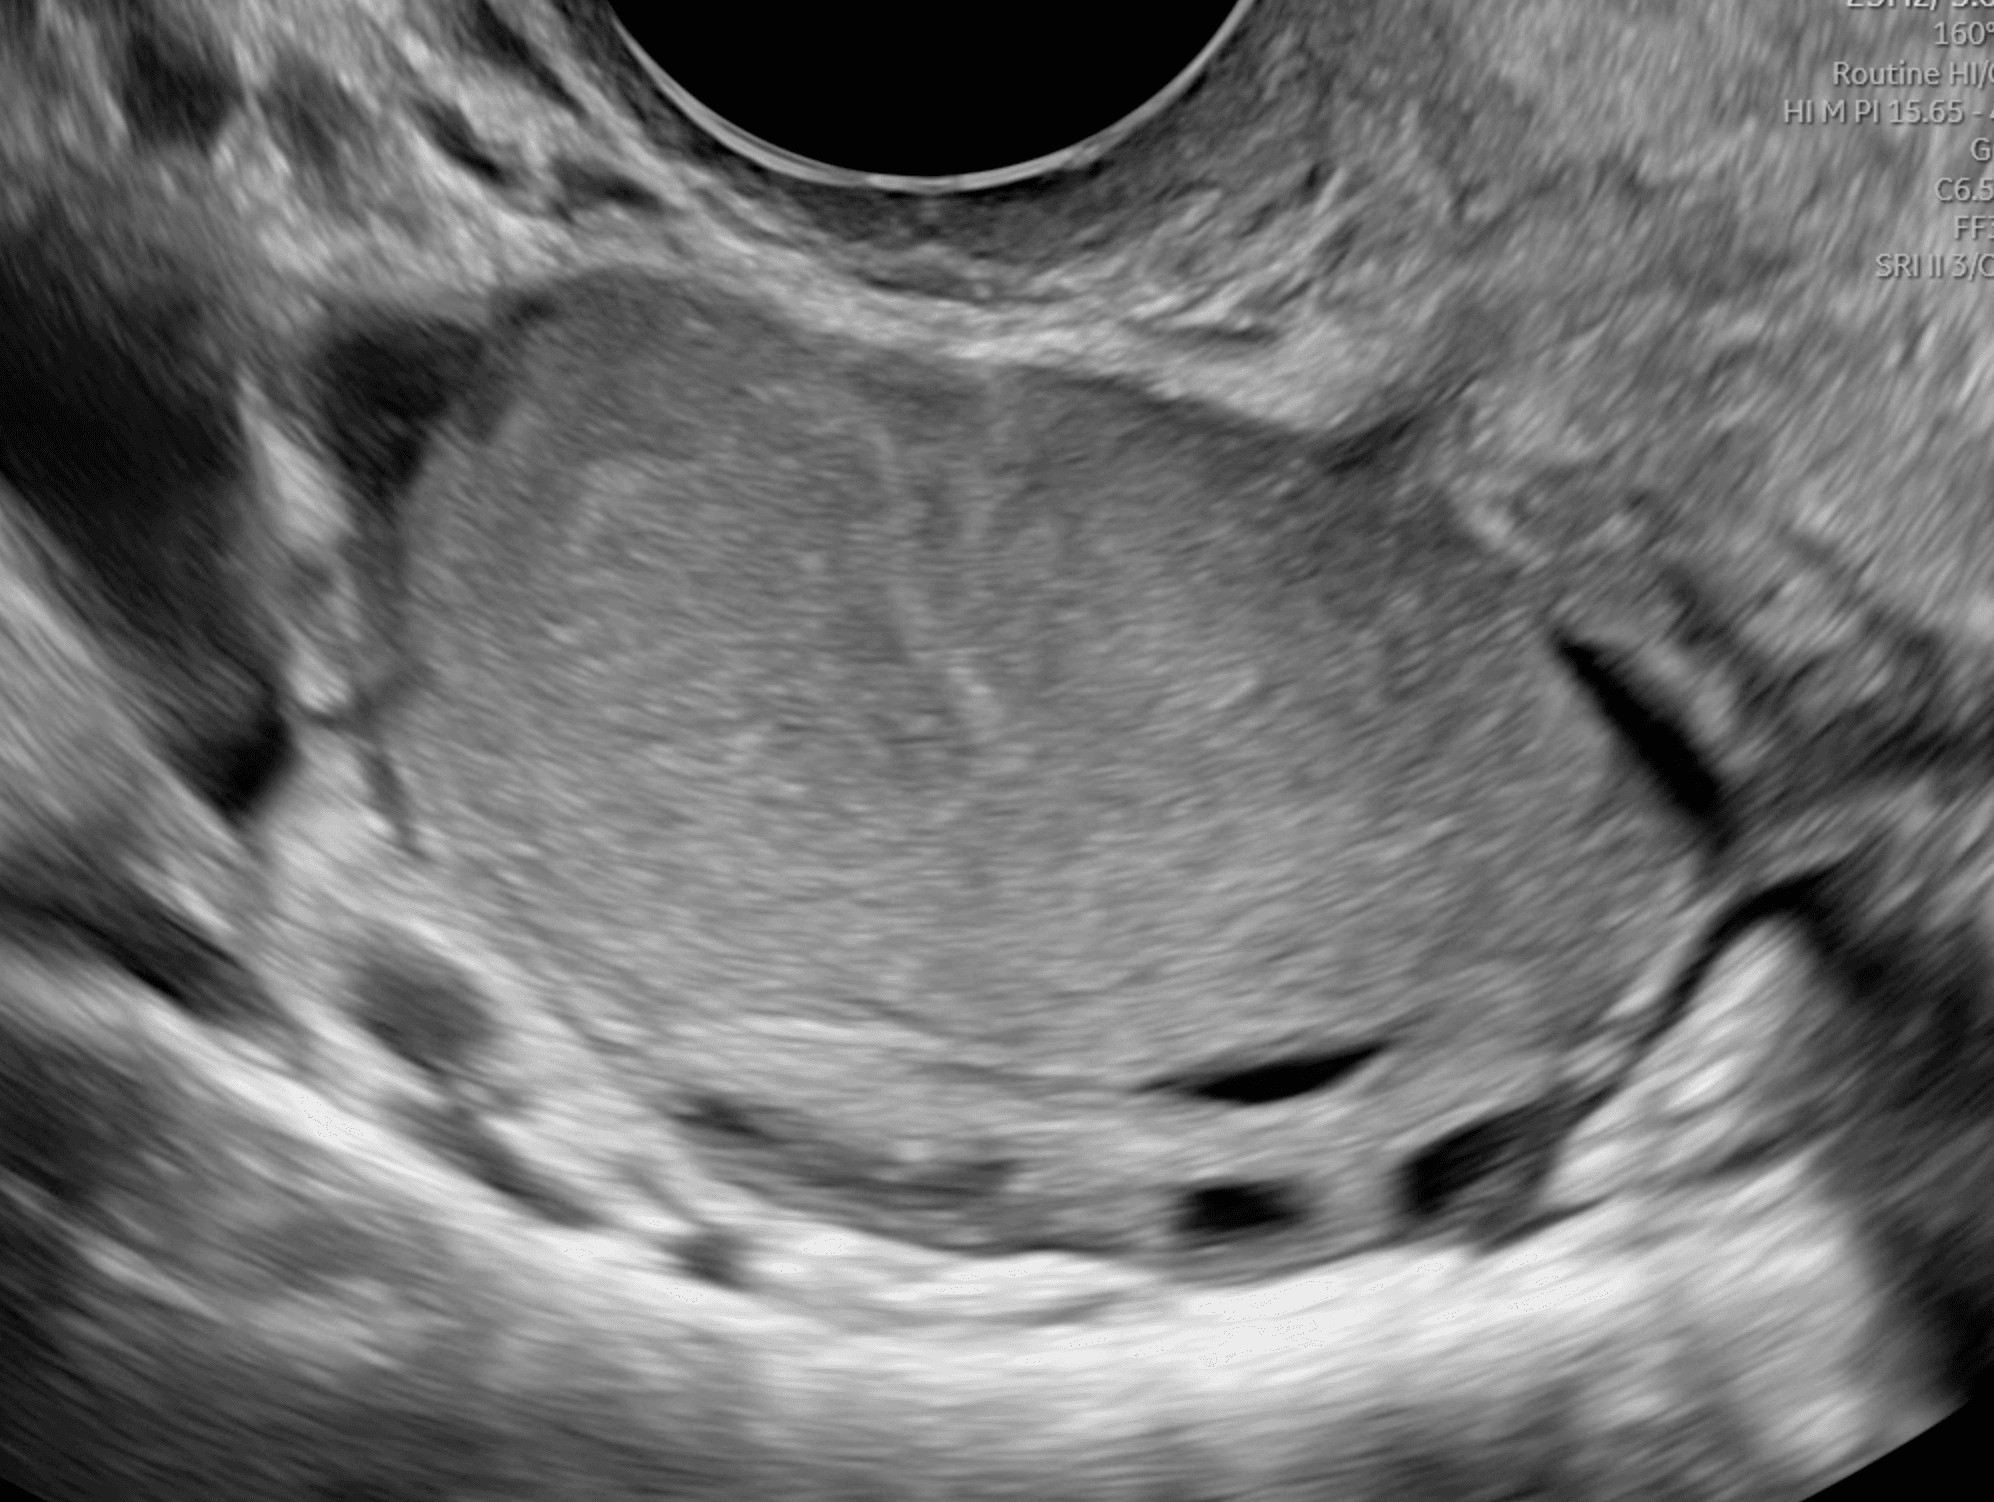

Cisti endometriosica (endometrioma ovarico)

Ecografia transvaginale che mostra una cisti ovarica endometriosica (o endometrioma). Si osservano alcuni follicoli ovarici, che dimostrano un tessuto ovarico sano attorno alla cisti.